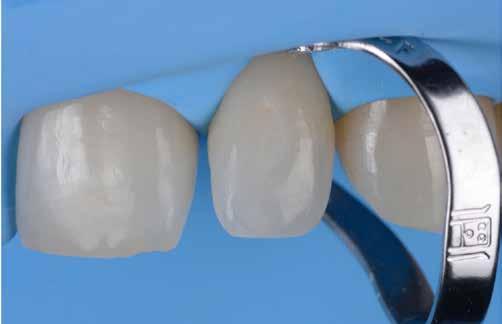

1. A kofferdámmal a legkritikusabb területen, amely megfelel a zenit és a kiemelkedési profilnak, RETRAKCIÓT hoz létre, amit semmilyen wax-uppal nem lehet megtenni (5. ábra).

2. A bukkális növekmény stabil kompozittal létrehozott szabadkézi felépítése, amely követi az Ön közvetlen látását és a fog megjelenését, ugyanolyan pontosan meghatározza a FORMÁT, mint egy wax-up. Más szóval, ez egy direkt wax-up.

3. A hátsó mátrixok OPTIMÁLJÁK az előzőleg felépített formát, és létrehozzák az ideális érintkezési pontot.

4. A hátsó kitöltés minden hézagot kiküszöböl, és tökéletes ZÁRÓDÁS-t hoz létre, különösen a restauráció legapikálisabb részén.

2-4. ábra: Gyakori problémák klasszikus megközelítéssel. 5. ábra: Tökéletes vészhelyzeti profil elülső szárnyas technikával. Dr. Jun Iwata, Japán jóvoltából.